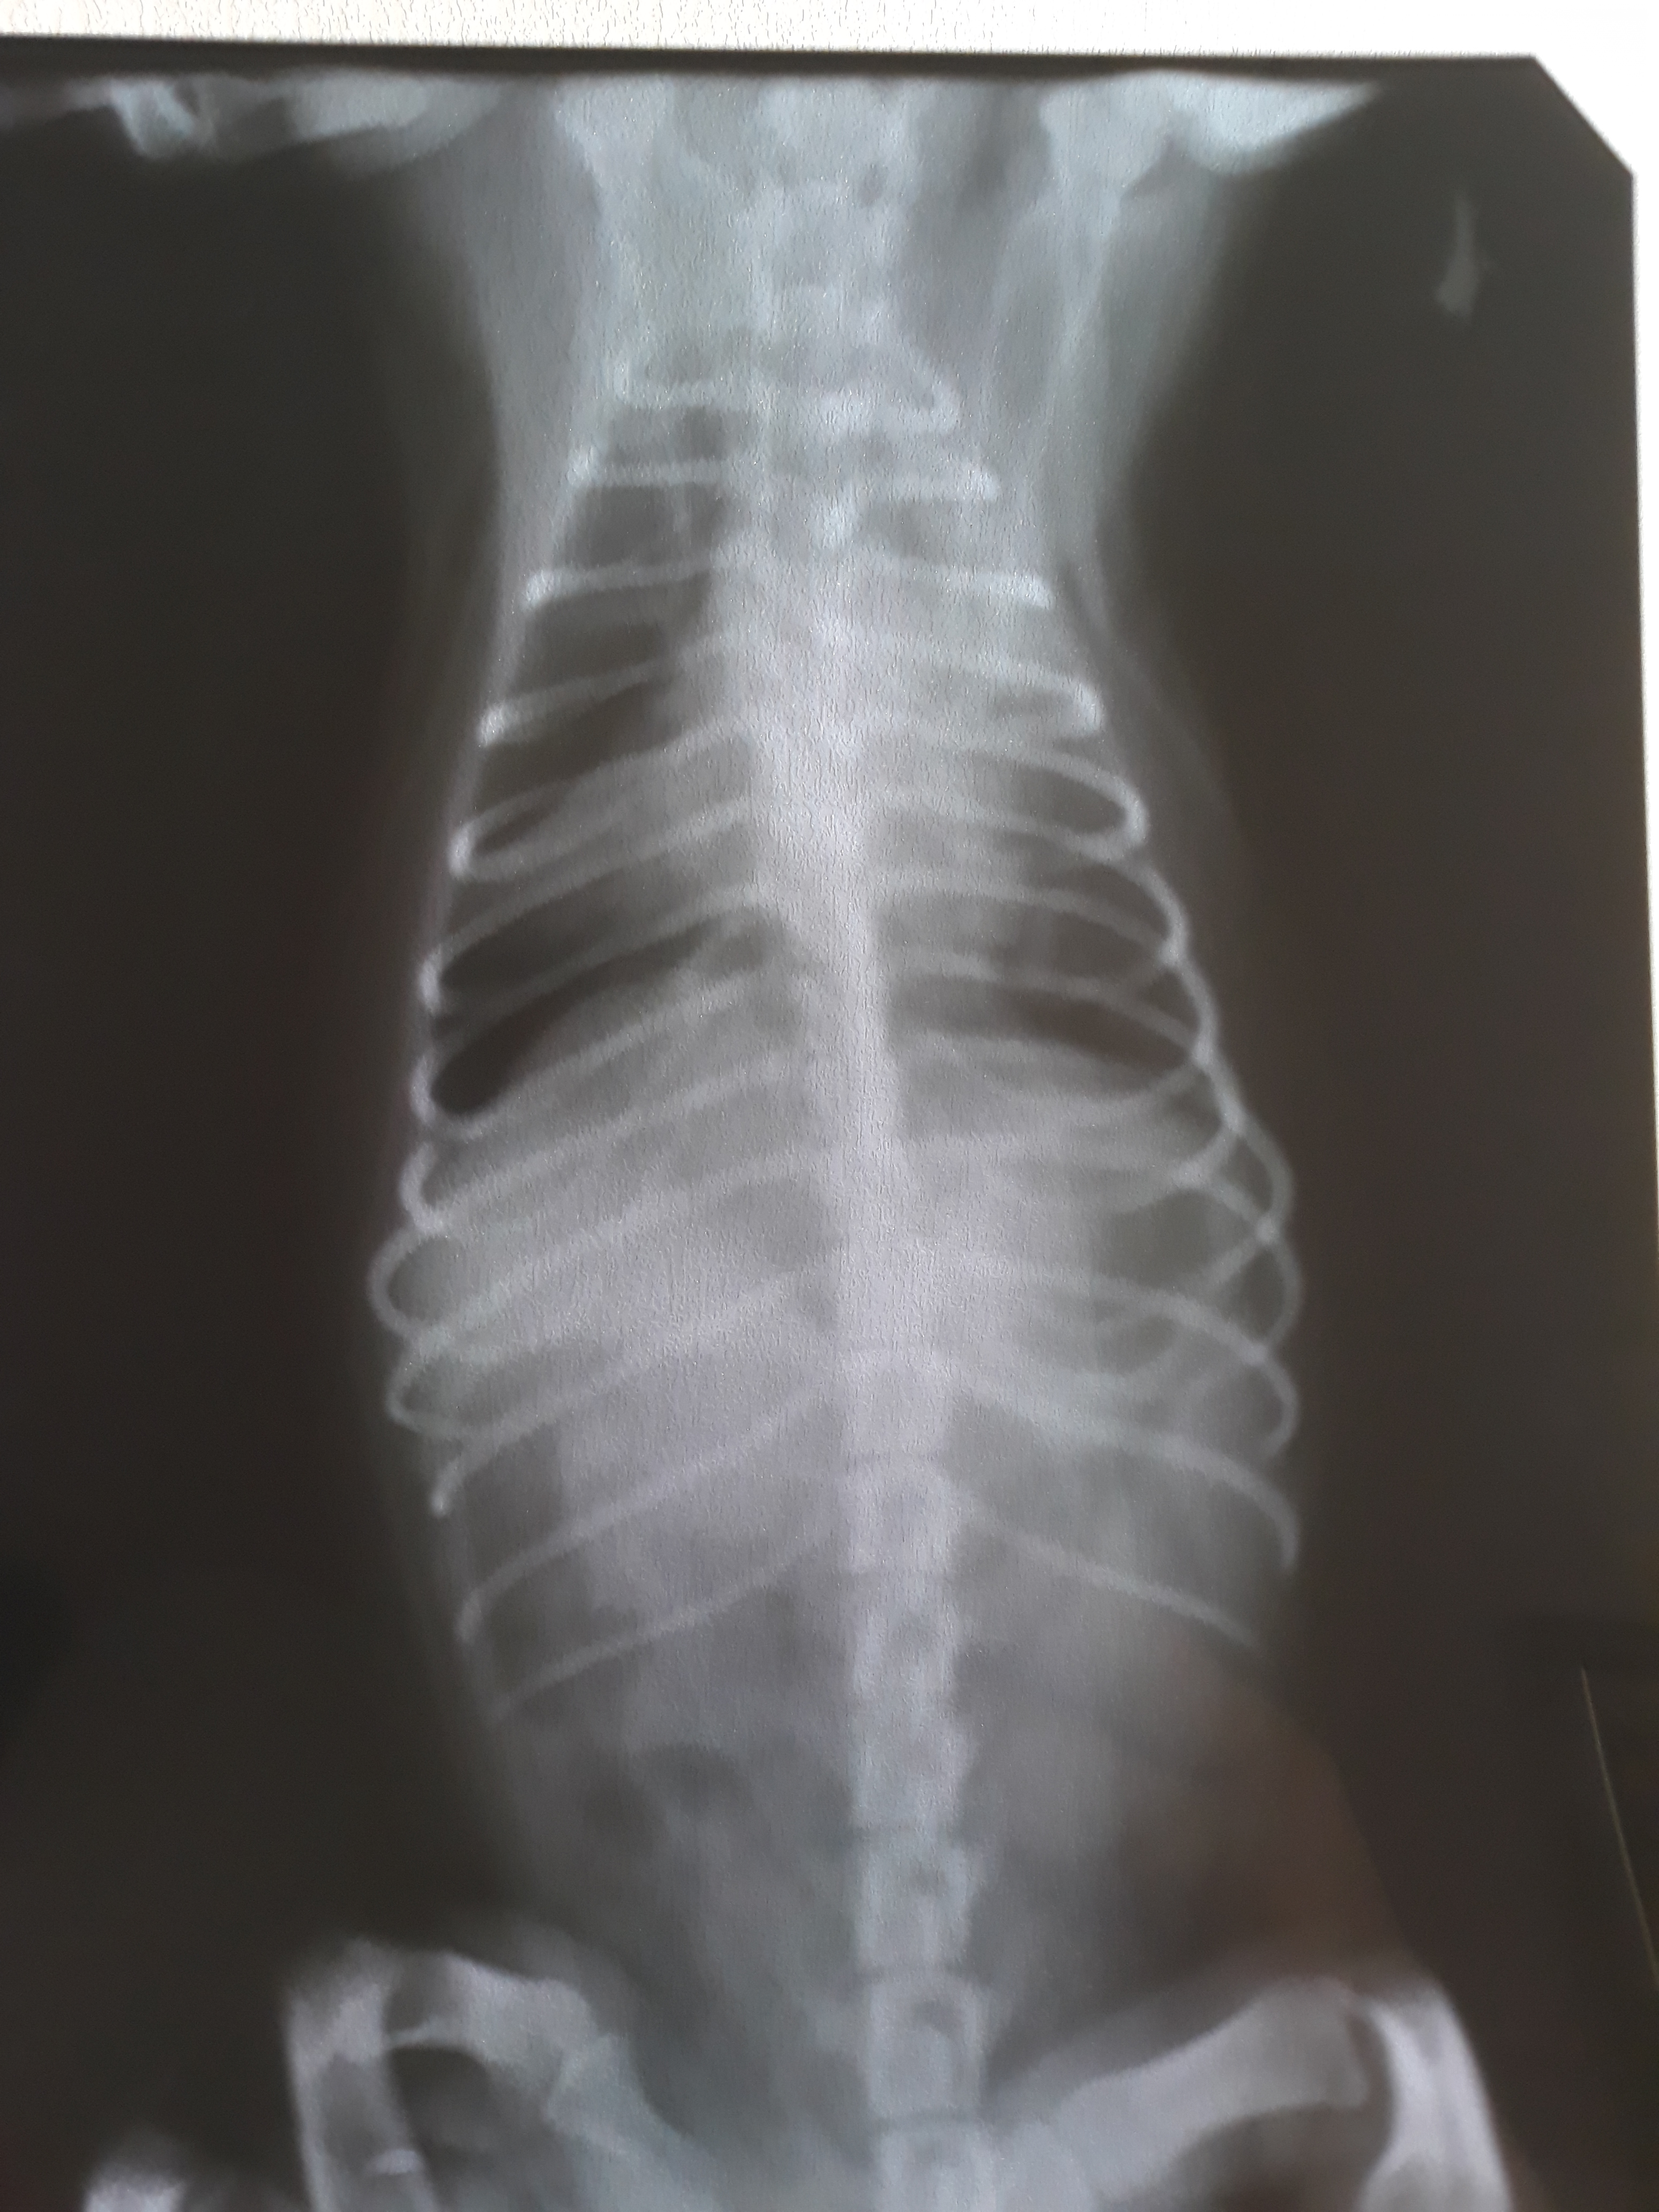

Только вернулись домой. Через час снова в клинику... Снимки пока не расшифровали,но мне кажется все плохо на них((( чуть позже выложу фото, может быть кто-то подскажет что-то...

Вот снимки...

Я не рентгенолог, конечно, но отчетливых признаков отека не вижу. Смущает состояние левого легкого, затенение верхней и средней доли.

Качество снимков еще не очень.

Ну, подождём заключение специалиста.